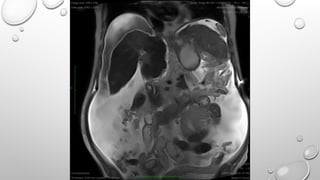

• BALANCED SSFP IS USED IN

CARDIAC IMAGING

FETAL IMAGING

ABDOMINAL IMAGING

SIEMENS : TRUE FISP

• BALANCED SSFPIS USED IN CARDIAC IMAGING FETAL IMAGING ABDOMINAL IMAGING SIEMENS : TRUE FISP MODIFICATIONS : CISS DESS